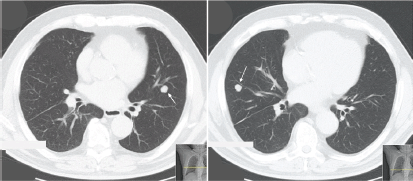

Seventeen years later, he started complaining of insidious but progressive asthenia. Chest X-ray revealed two nodular opacities in the lower lobes of both lungs and thoracic CT scan presented multiple bilateral pulmonary nodules (middle right lobe, lingual, and apical segment of the left lower lobe) (Figure 3).

Figure 3. Thoracic CT scan (patient #3) exhibiting bilateral nodes. Arrow indicates lesion in the left lung (apical segment of the lower lobe) and right lung (anterior segment of the lower lobe).